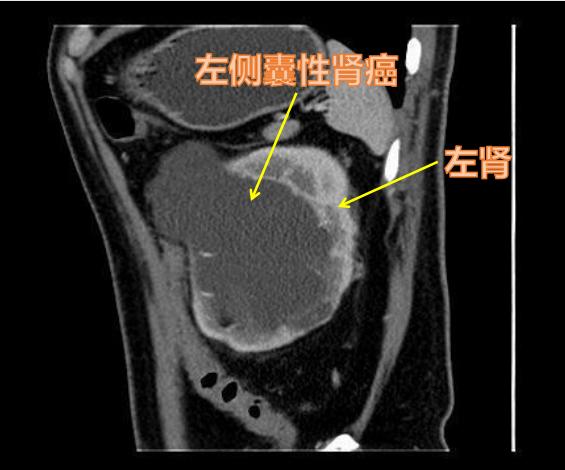

囊性肾癌在肾细胞癌中约占4%~15%,多发生于男性病人,肿瘤细胞来源于肾小管的上皮细胞,以囊肿的形式呈膨胀性生长,慢慢形成一个或者多个大小不一的单房或多房囊性肾癌。它的临床症状和表现包括患侧腰部疼痛、肉眼或显微镜下血尿、腹部包块、食欲不振、消瘦、反复低热等。有时候通过B超检查,难以区分囊性肾癌与单纯性肾囊肿,常常需要高分辨率的增强CT扫描才能够进一步辨别。

囊性肾癌周围分界不清晰!